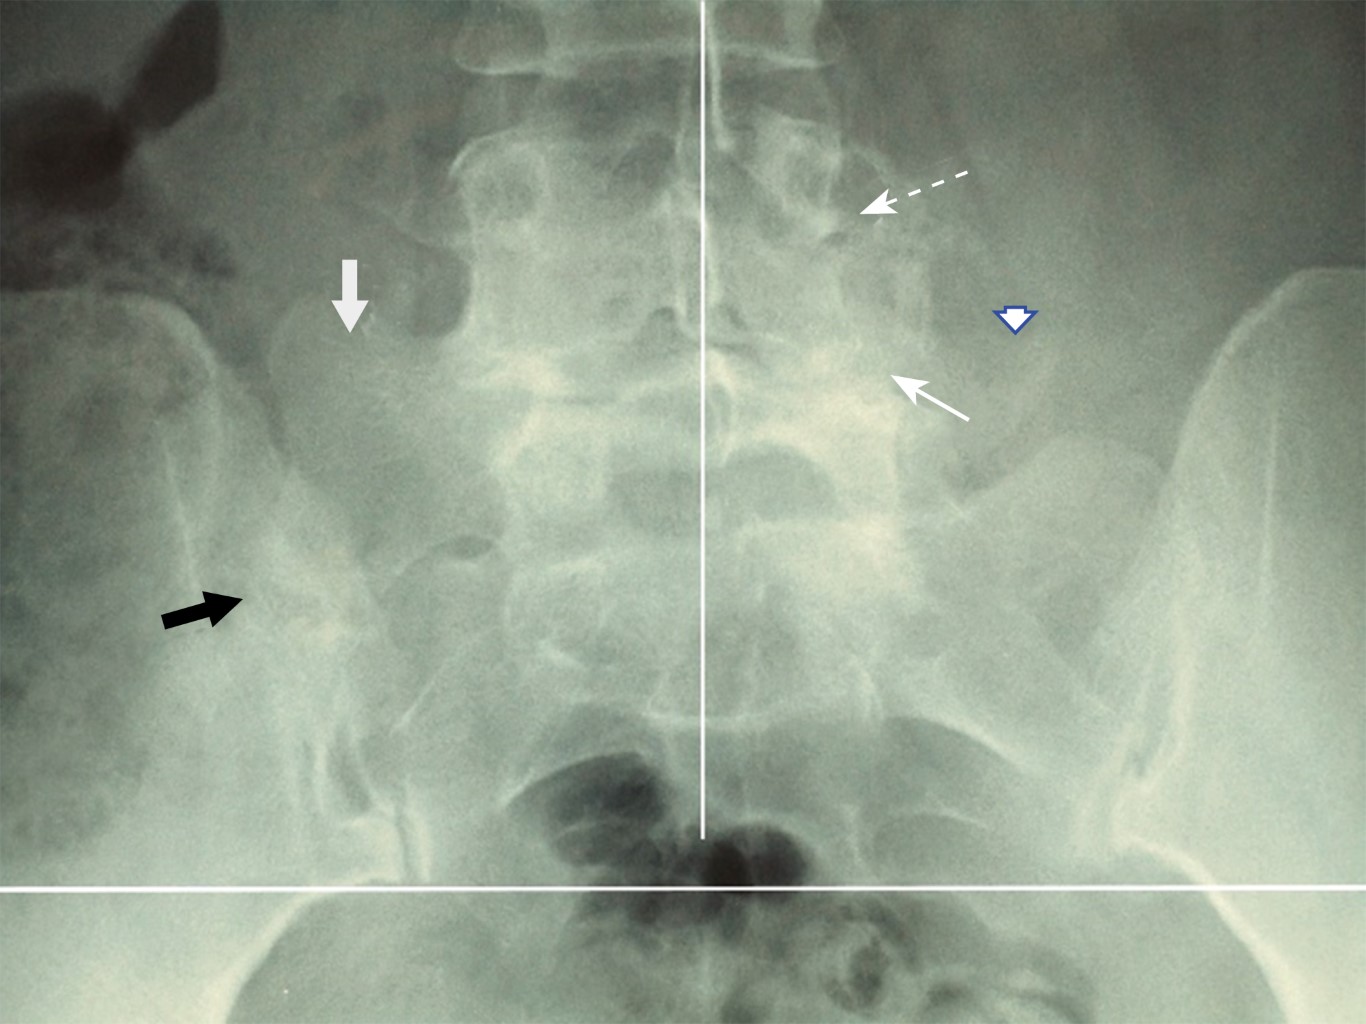

Paciente masculino de 33 años de edad con antecedentes de cuadros de lumbalgia moderada desde los 18 años de edad (de uno a tres cuadros por año, con duración de síntomas de menos de una semana por episodio); relata haber subido 7 kilos de peso en el último año, por lo que decidió someterse a programa de ejercicio en los dos últimos meses (trote de 5 kilómetros alternando con ejercicios aeróbicos en gimnasio). A los 10 días del inicio de ejercicio presentó lumbalgia con intensidad de 6 a 8 en EVA, con irradiación a nalga derecha y cara anterolateral de muslo izquierdo por arriba de rodilla que no respondió a antiinflamatorios habituales utilizados por el paciente (naproxeno 500 mg BID), por lo que acude a rehabilitación. A la exploración: marcha de características normales; postura: elevación discreta de hombro derecho, desnivel pélvico por acortamiento de miembro pélvico derecho, abdomen globoso por panículo adiposo e hiperlordosis lumbar. Dolor a la presión de músculos paravertebrales lumbares bilateral que se incrementa con movimientos de rotación, dolor a la presión de articulación sacroiliaca derecha, siendo positivos los signos de Patrick, Gaenslen y de Yeoman para sacroiliaca derecha y negativos para la izquierda; signo de Lasègue negativo bilateral, arcos de movimiento de extremidades pélvicas completos, examen clínico muscular indicando: abdominales 3/5, resto 5/5; sensibilidad, reflejos osteotendinosos, pulsos y llenado capilar normales. Con diagnóstico de síndrome facetario L4/L5 izquierdo y probable sacroileitis derecha. Se solicitaron radiografías simples anteroposterior y lateral de columna lumbosacra en bipedestación (Figura 1) encontrando: sacralización de la quinta vértebra lumbar con megaapófisis transversa derecha (flecha gris) al compararse con apófisis transversa izquierda de L5 (cabeza de flecha) formando pseudoarticulación con el ilion derecho (flecha negra) y artrosis facetaria L4/L5 izquierda (flecha blanca delgada), asociada con laterolistesis derecha del cuerpo de L4 (flecha punteada). Se estableció diagnóstico de síndrome de Bertolotti tipo IIA.

Figura 1